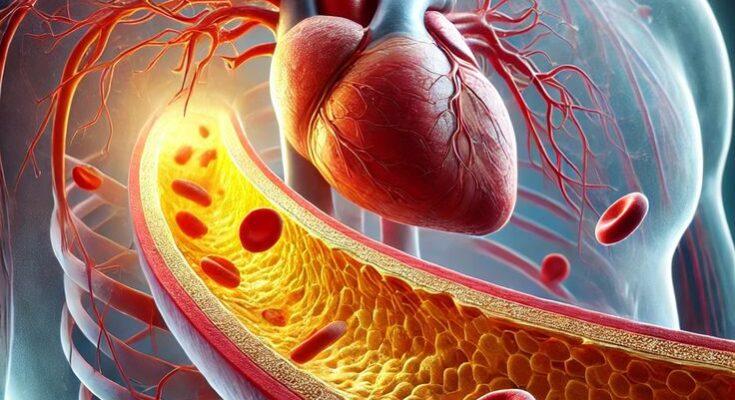

आज की तेज़ रफ्तार जिंदगी में हार्ट अटैक एक गंभीर स्वास्थ्य समस्या बन चुकी है. अक्सर लोग यह मानते हैं कि हार्ट अटैक अचानक होता है, लेकिन हकीकत यह है कि शरीर कई साल पहले ही इसके संकेत देना शुरू कर देता है. यदि इन लक्षणों पर ध्यान दिया जाए तो समय रहते सावधानी बरतकर इस खतरे से बचा जा सकता है.

हार्ट अटैक किन कारणों से आता है?

हार्ट अटैक का सबसे बड़ा कारण धमनियों में कोलेस्ट्रॉल और चर्बी जमना है, जिससे खून का प्रवाह रुक जाता है. इसके अलावा: